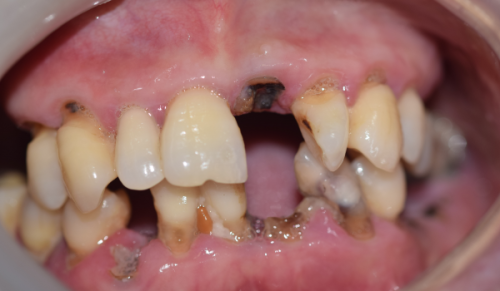

术后护理:术后护理对种牙修复至关重要。患者要规范使用漱口水,这样可以预防感染。在术后1周内,建议进流食,避免食物对伤口造成刺激。另外,吸烟也会影响种牙的修复。吸烟者的愈合时间可能会延长30% - 50%。因为香烟中的有害物质会影响血循环,从而影响伤口的愈合。所以,为了能更快地修复,患者在种牙前后更好戒烟。

个体差异:每个人的身体状况不同,种牙修复时间也会有差异。比如糖尿病患者,他们的骨结合时间平均会延长1个月。这是因为糖尿病会影响身体的代谢功能,导致伤口愈合缓慢。还有骨质疏松患者,他们的骨质比较疏松,种植体与颌骨结合可能会更困难,所以需要评估植骨的必要性。如果需要植骨,修复时间也会相应延长。